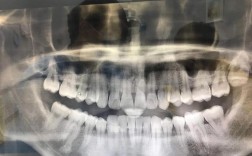

牙齿矫正是通过正畸装置对牙齿施加持续、轻柔的力,引导牙槽骨改建,使牙齿移动至理想位置,从而达到排列整齐、咬合正常、改善面部美观的目的,矫正对象不仅限于青少年,成年人也可进行矫正,但需考虑牙周健康状况、骨骼发育情况等因素,常见矫正方法包括传统金属托槽矫正、陶瓷托槽矫正、隐形矫正和舌侧矫正,传统金属托槽性价比高,强度大,但美观性差;陶瓷托槽接近牙齿颜色,美观性较好,但脆性较大;隐形矫正通过透明牙套施加力量,可自行摘戴,美观舒适,但对患者依从性要求高,需每天佩戴20小时以上;舌侧矫正将托槽粘在牙齿内侧,完全隐形,但技术难度大、价格高,且初期异物感明显,矫正过程通常包括初诊检查(拍摄X光片、取模、制定方案)、戴入矫治器、定期复诊调整(每4-6周一次)、拆除矫治器及佩戴保持器等阶段,矫正期间需注意口腔卫生,避免食用过硬、黏性食物,防止托槽脱落;同时需定期复查,监控牙齿移动情况,确保矫正效果稳定。